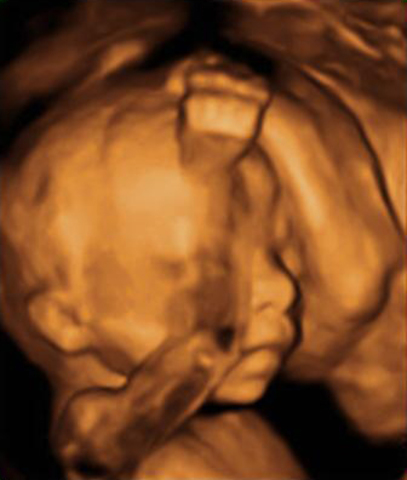

El desarrollo anatómico y funcional ya le permite al bebé comenzar a manifestar expresiones faciales: fruncir el entrecejo, arrugar la cara, sonreír, etc. El bebé ya puede hacer un puño y su actividad es intensa; la masa muscular es tal que a partir de esta semana la futura madre puede comenzar a sentir a su bebé ya puede mover la pared uterina desde adentro. Los ojos del bebé comienzan a ser sensibles a la luz. En las hembritas ya se han formado un millón de óvulos en los ovarios.